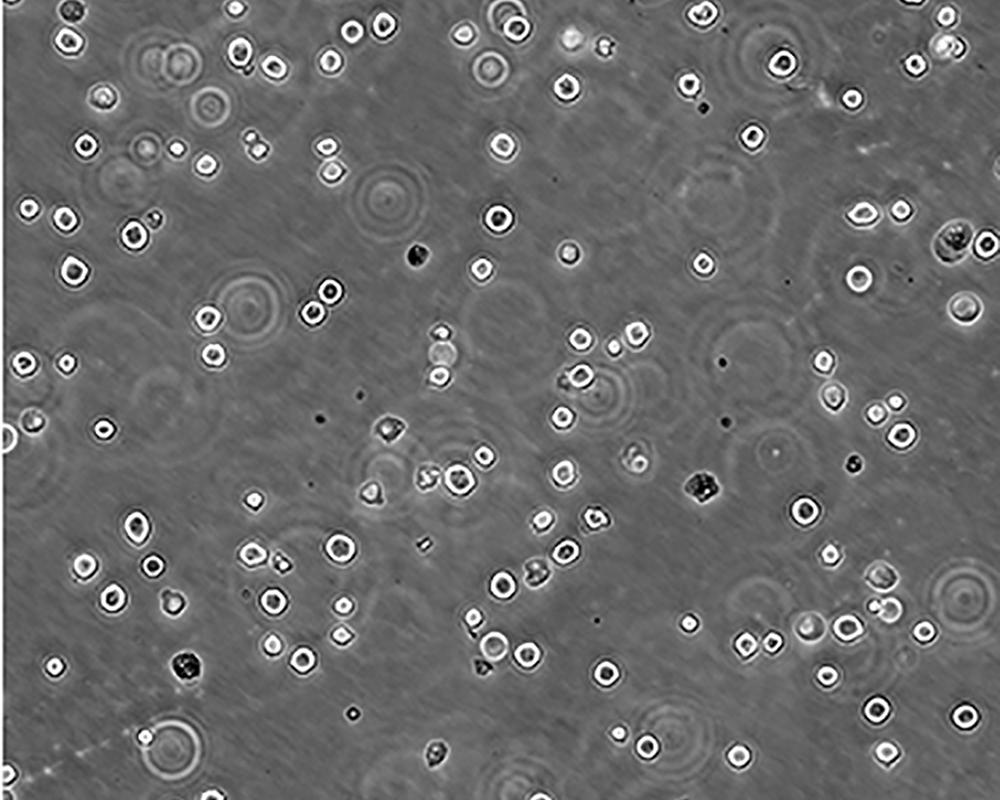

生長特性 suspension

形態特征 lymphoblast

傳代方法 1:2-1:4

細胞描述 The cell population has been characterized as highly undifferentiated and of the granulocytic series. Studies conducted by Anderson, et al. , on the surface membrane properties led to the conclusion that the K-562 was a human erythroleukemia line. K-562 blasts are multipotential, hematopoietic malignant cells that spontaneously differentiate into recognizable progenitors of the erythrocytic, granulocytic and monocytic series. The effect of inducers on sublines derived from the original K-562 cell line have been reviewed by Koeffler and Golde. Karyological studies on various K- 562 sublines have been classified into three groups(A,B,C) by Dimery, et al. The strain obtained by the ATCC most closely resembles the B population. Occurrence of the Philadelphia chromosome, however, was of much lower frequency; none detected in 15 metaphases examined. The line is EBNA negative.